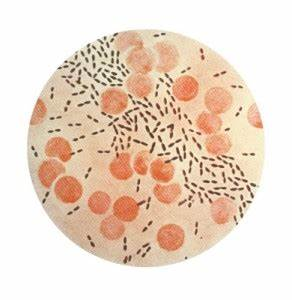

脊柱术后感染很危险

脊柱术后感染是一种潜在的严重并发症,文献报道其发生率为0.7–8.5%。

脊柱术后感染最常见的危险因素有输血、脑脊液漏、尿路感染、硬脑膜损伤、肥胖、糖尿病和翻修手术;常见临床表现为发热、疼痛和神经症状;炎症实验室参数升高是感染的明显迹象。

颅内感染是脊柱术后感染中比较严重的一种,属于高危重症,致死率极高。

颅内感染示意图